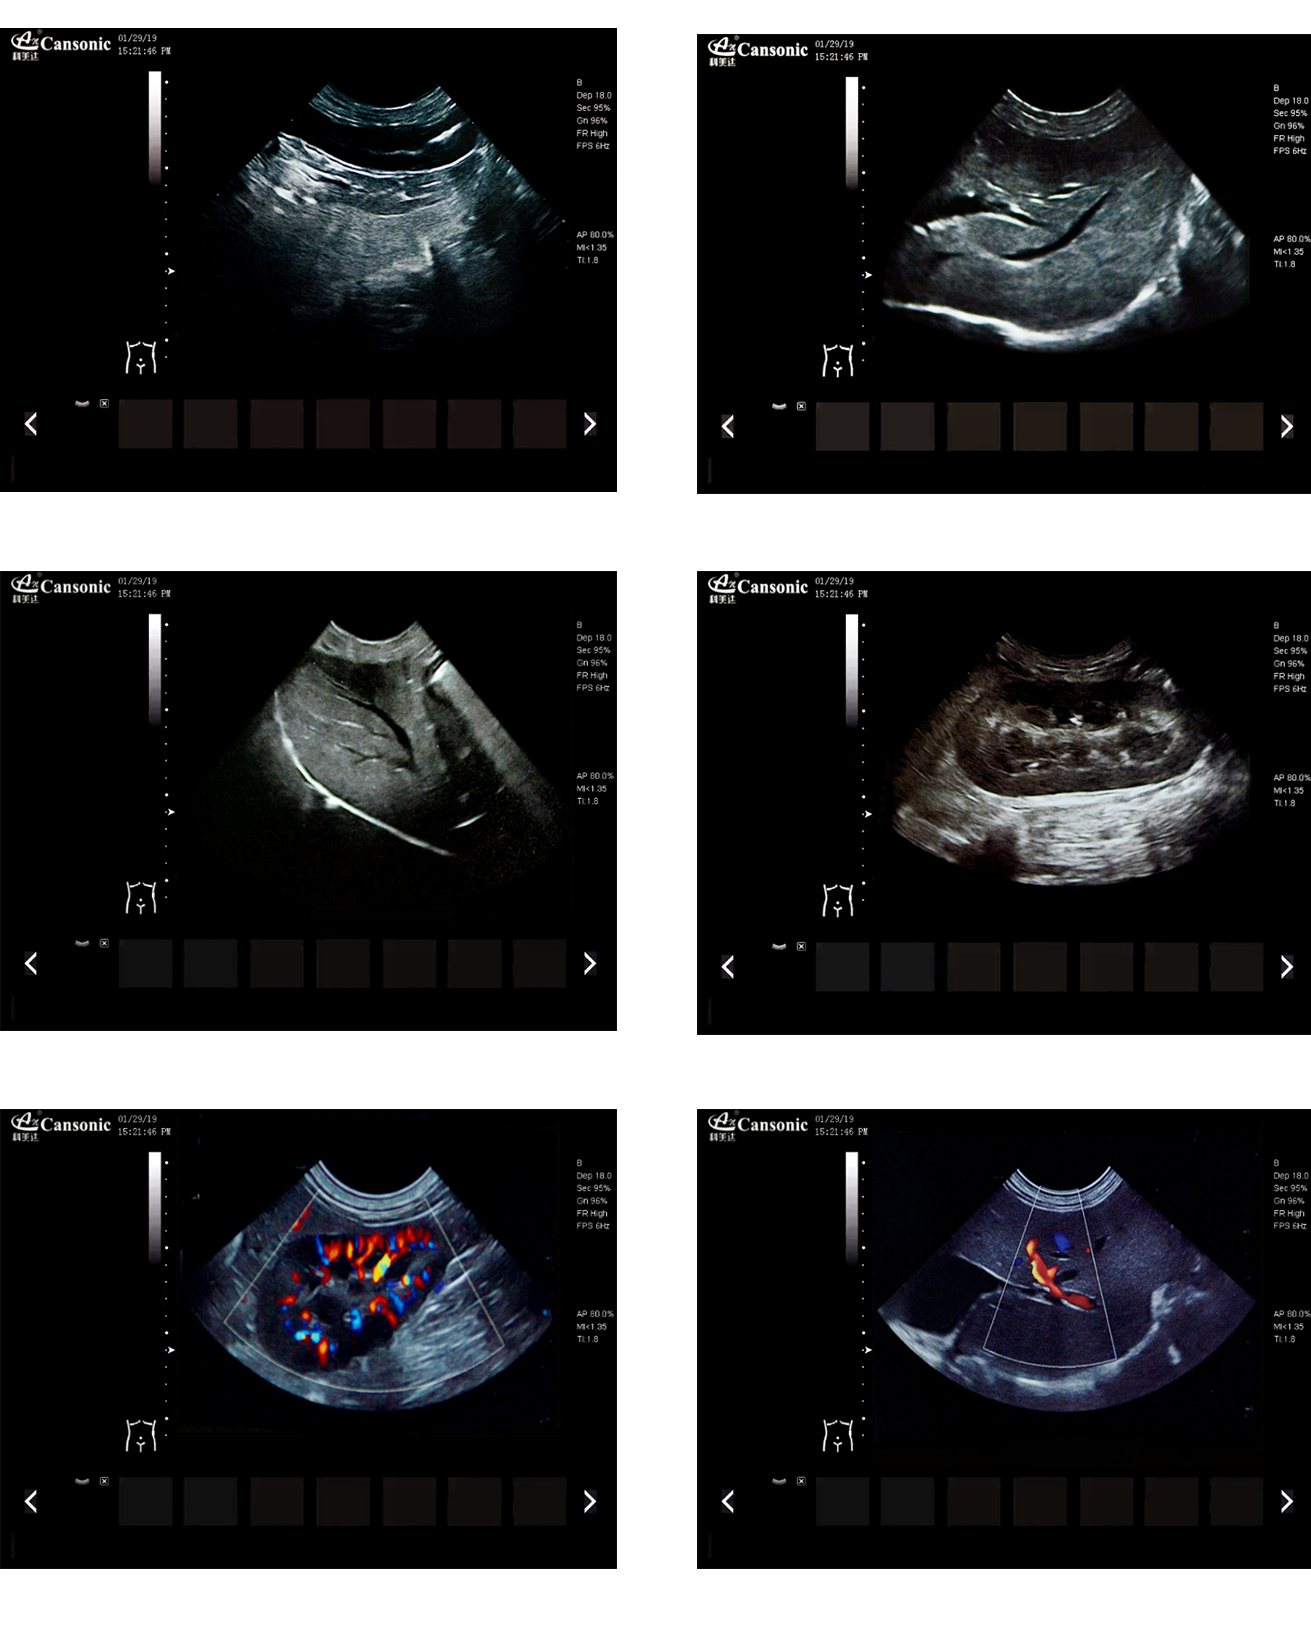

K2V

產(chǎn)品特點(diǎn):

1、薈萃前沿成像技術(shù),實(shí)現(xiàn)高精與靈便的完美融合,提供完整的動物彩超診療方案

2、專業(yè)的獸用測量軟件,簡捷的工作流,適合犬、貓、馬、牛、羊等 各類大小動物

3、iClear斑點(diǎn)噪聲抑制抑制噪聲干擾,使動物組織結(jié)構(gòu)更清晰

4、具有廣泛的動態(tài)范圍,顯示出色的組織均勻性,減少了偽影及噪聲

5、精細(xì)血流識別技術(shù),增加了可疑病變更多的信息分析

6、先進(jìn)的算法帶來清晰的穿刺針顯示,降低穿刺活檢操作難度

7、圖像優(yōu)異,同時(shí)性能穩(wěn)定,每天能進(jìn)行大量的動物超聲檢查

8、輕巧的機(jī)身,耐摩損的把手,適應(yīng)各種復(fù)雜的動物使用環(huán)境

臨床圖示